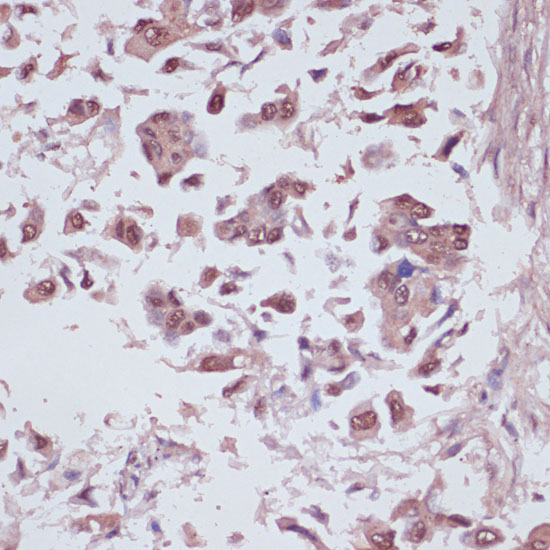

Immunohistochemistry of paraffin-embedded human lung cancer using U2AF1 at dilution of 1:100 (40x lens).